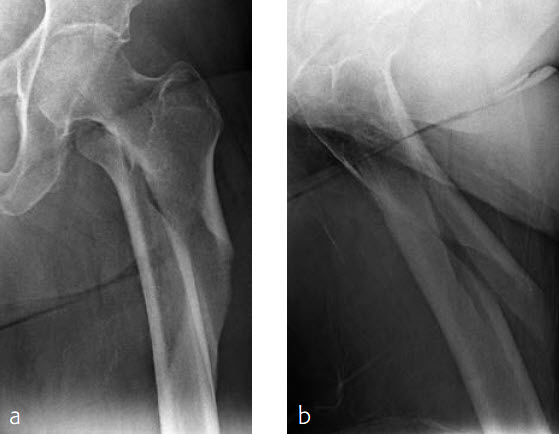

Case 1: Subtrochanteric femur fracture

An 86-year-old patient fell at home while dressing, sustaining a subtrochanteric left femur fracture (Fig 1). The CT scan confirmed no involvement of the intertrochanteric region or the piriformis fossa. Fixation was with FRN for piriformis fossa entry point in reconstruction locking mode and transverse locking (Fig 2).